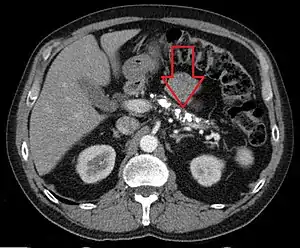

![]() Знімок КТ в аксіальній проекції демонструє кальцифікати в підшлунковій залозі у пацієнта з хронічним панкреатитом Знімок КТ в аксіальній проекції демонструє кальцифікати в підшлунковій залозі у пацієнта з хронічним панкреатитом | |